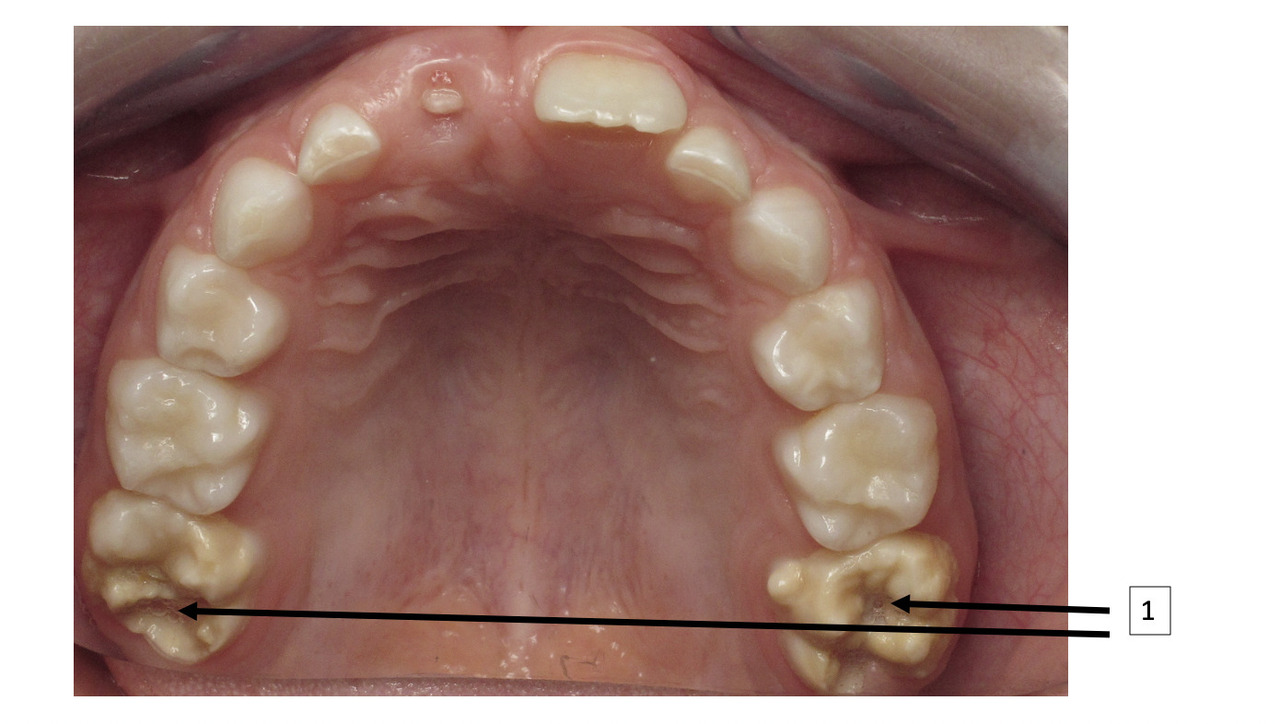

La MIH est une anomalie de la structure de l’émail se traduisant par un défaut qualitatif de l’émail sur au moins une des quatre premières molaires permanentes, associé ou non à une atteinte d’une ou plusieurs incisives permanentes (fig. 1).1 Les autres dents permanentes sont plus rarement atteintes. On peut également retrouver une atteinte similaire au niveau des deuxièmes molaires temporaires, appelée alors HSPM (hypomineralised second primary molar). Un enfant atteint de HSPM a cinq fois plus de risque d’être atteint de MIH en dentition permanente.

Le diagnostic repose sur l’observation clinique : des opacités (taches) blanches, beiges ou brunes de taille variable sont présentes et visibles sur les dents atteintes (fig. 1, 2 et 3). Les opacités, bien démarquées, sont présentes dès l’éruption de la dent et leur taille ne se modifie pas dans le temps. Cependant, l’émail étant plus fragile, des fractures amélaires post-éruptives sont observées, entraînant des pertes de substance surtout au niveau des molaires qui sont soumises aux forces de mastication. L’atteinte est asymétrique, c’est-à-dire que pour un même patient sa sévérité peut varier d’une dent à l’autre, allant d’une absence d’atteinte à une perte de substance importante, en passant par une dyschromie discrète. Si une tache est observée sur une incisive permanente, il est important d’examiner les molaires permanentes. Le médecin généraliste doit alors évoquer une anomalie de structure dentaire et orienter le patient vers un chirurgien-dentiste. Celui-ci confirmera le diagnostic de MIH ou établira un autre diagnostic. Les diagnostics différentiels sont :